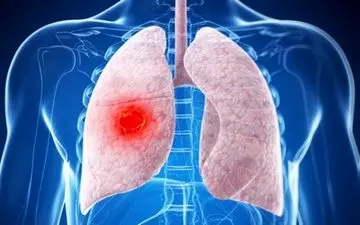

سرفه یک مکانیزم مفید دفاعی بدن است. اما وقتی دائمی شد، علامت بیماری ریوی است.

افراد نباید سرفه های آزاردهنده یا خس خس خفیف سینه را نادیده بگیرند چراکه اینها می توانند علائم بیماری ریه نظیر آسم،…

مطالعه ای جدید نشان می دهد که ژن های برخی از افراد سیگاری احتمال ابتلای آنها به نوعی بیماری ریوی مرگبار را تا ۷۲ درصد…